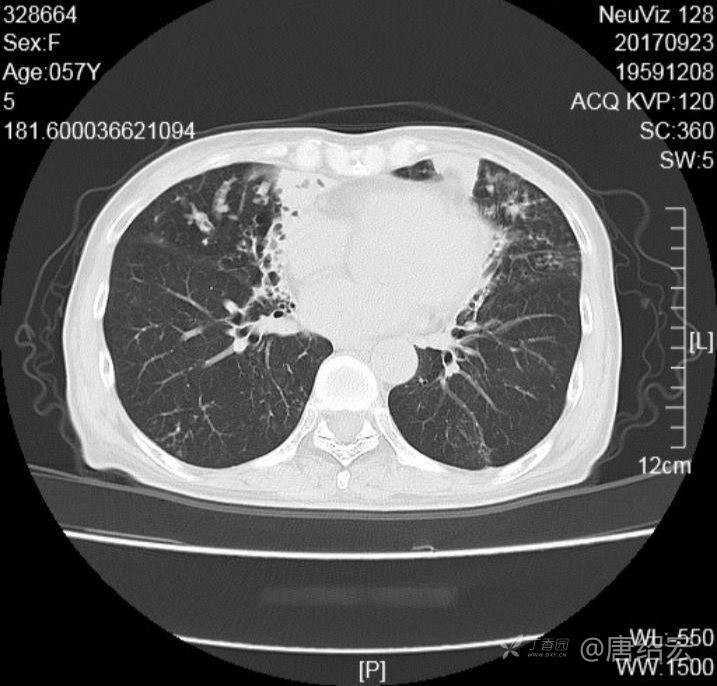

女,57岁,

主诉:发热、咳嗽、咯黄痰,胸闷3天入院。

铜绿假单胞菌性肺炎 (12)

铜绿假单胞菌感染 (20)